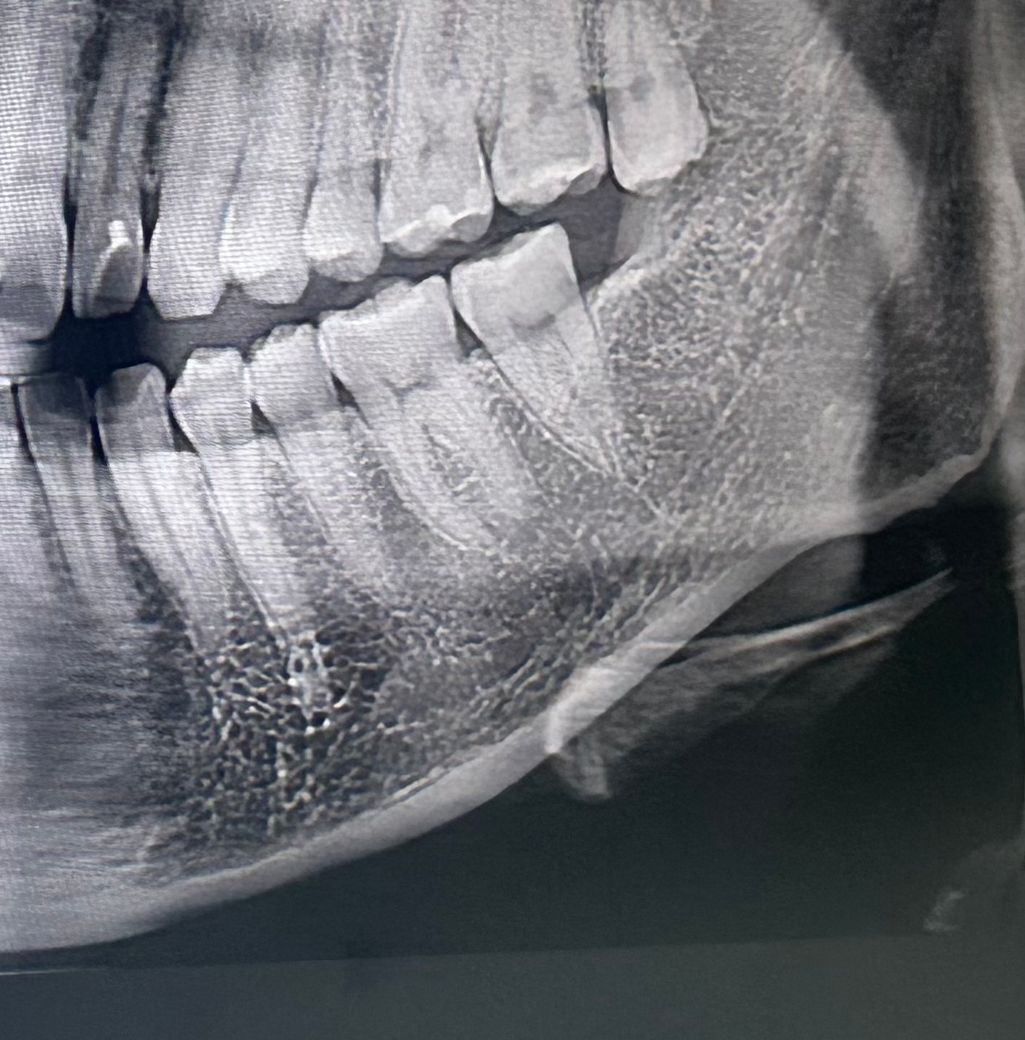

맨 왼쪽 어금니가 가만히 있을때 약하게 욱신거려요

최근까지 치과에 갔을때 맨 왼쪽 어금니에 아무 문제가 없다고 들었습니다

찬물 뜨거운물 음식씹을때 바람 어느것에도 시리거나 아프지 않구요

대신 가만히 있을때 욱신..? 우리하다..? 라고 표현해야할까요

이건 무슨 증상일까요? 레진이 많이 닳아잇긴 하다고 하는데 그 증상인가요..? 치실을 해서 잇몸이 다친건가요?

사진은 2주전에 찍은 사진입니다

또 사랑니 뽑아야할까요?

• 1번 째 사진

사진만으로는 판별이 어렵습니다. 치과에 가서 검진 해보시는 게 좋겠고 사랑니는 빼는 게 좋아보입니다.

증상 자체는 어금니의 충치는 아닌 것으로 보여집니다. 다만 사랑니가 맹출되어 있고 해당 부분에 치태 및 음식물이 많이 고여 있다면 사랑니로 인하여 주변 잇몸 질환일 가능성이 있습니다. 따라서 해당 부분에 대해 검사를 해보시는 것을 권해드리며 관리가 되지 않고 있다면 사랑니를 발치하는 것이 좋습니다.

심하게 아픈 것이 아닌 신경이 쓰이는 정도인 경우 크게 문제가 되지 않을가능성이 높습니다. 하지만 통증이 심해지거나 붓기 발생시에는 치과 진료가 필요로 되며, 만약 레진이나 사랑니에 문제가 있는 경우에는 조치를 받길 권합니다.